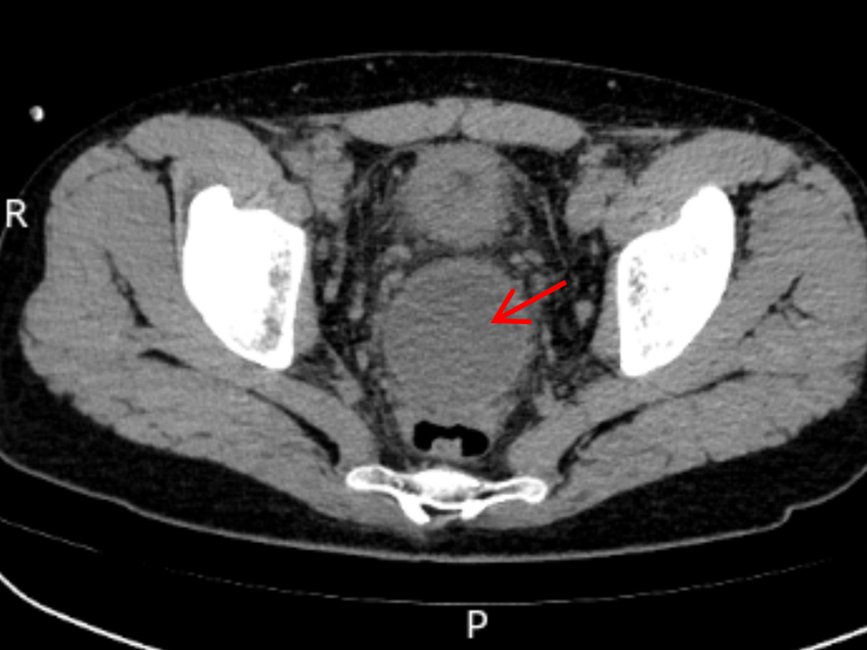

术前CT显示直肠前方一直径5cm圆形脓肿

患者数月前因阑尾穿孔引发腹腔及盆腔多处包裹性积液,在外院实施CT引导下腹腔双侧穿刺引流术时发现,盆腔积液位置极深,病灶前有膀胱遮挡、后有直肠遮蔽,常规超声及CT引导均无法完成穿刺引流;而外科开腹手术不仅视野受限、创伤较大,患者接受度也较低。迁延不愈的病情让患者持续低热,尿频、尿急、肛门下坠感等不适反复折磨,腹部留置的两根引流管更让他身心俱疲,生活质量直线下降。一筹莫展之际,患者转诊至青大附院市南院区,消化内科团队与急诊外科、放射科等多学科充分研讨,决定为患者实施超声内镜引导下经直肠盆腔脓肿穿刺引流置管术。